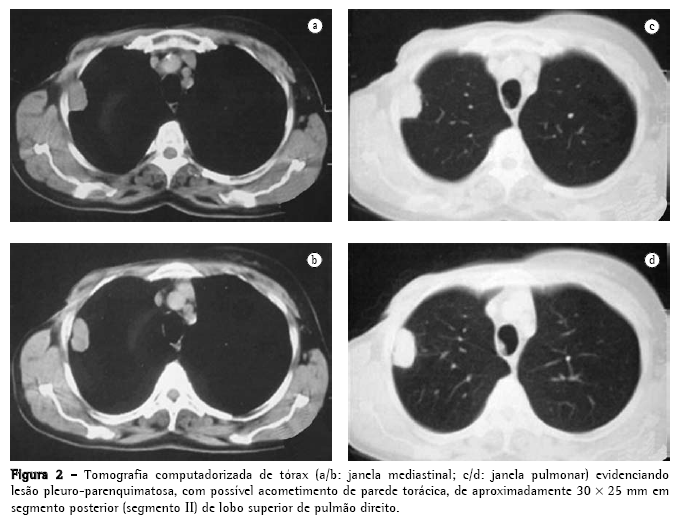

Foi então realizada tomografia computadorizada de tórax que identificou um nódulo pulmonar pleuro-parenquimatoso de aproximadamente 30 × 25 mm (Figura 2) em pulmão direito. Assim foi aventada a hipótese de metástase pulmonar do carcinoma de mama previamente operado, sendo indicada biópsia para confirmação diagnóstica.